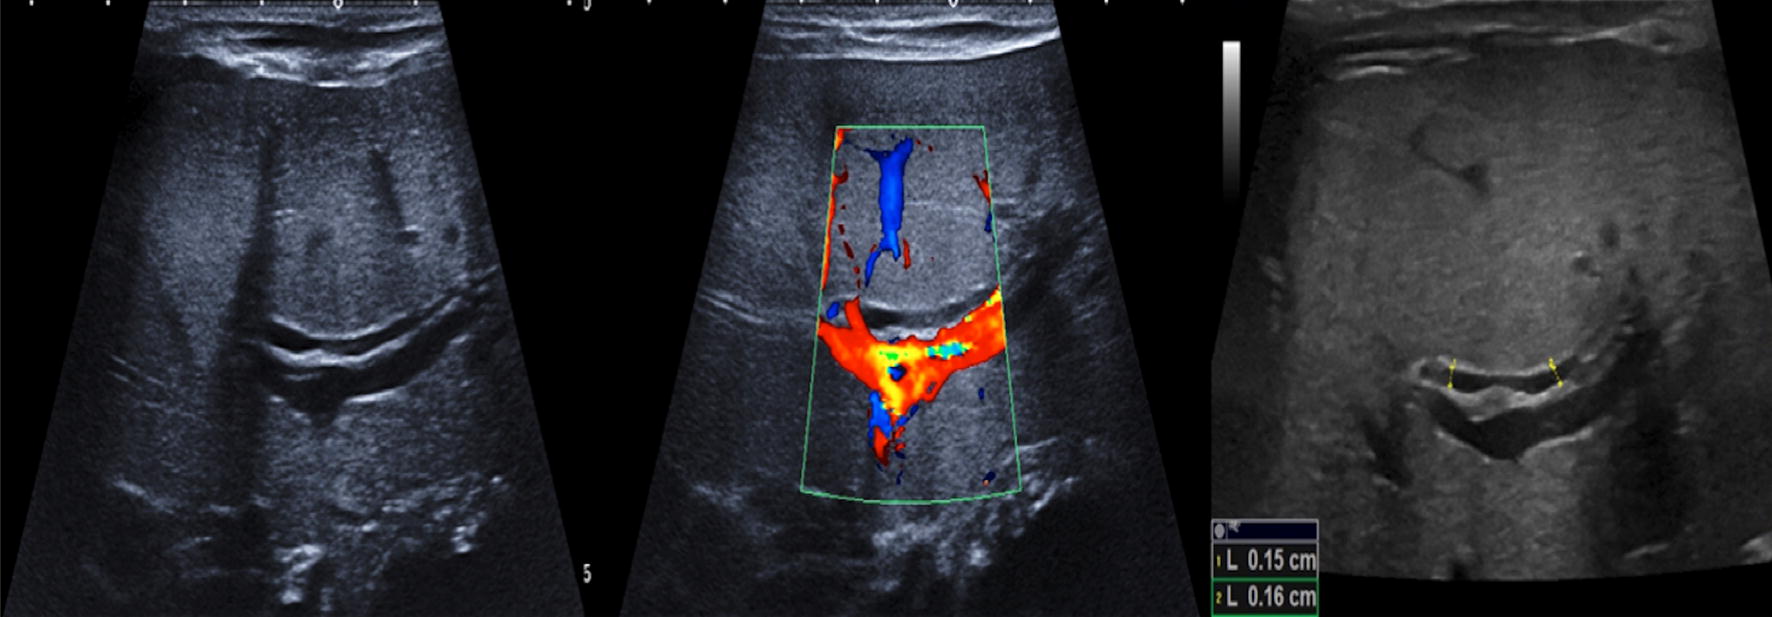

Monitoring intrahepatic cholestasis of pregnancy using the fetal Cholestasis Ultrasound Images cholestasis represents an impaired secretion of bilirubin by hepatocytes, manifesting with high blood levels of conjugated bilirubin and. biliary atresia is a congenital biliary disorder that is characterized by an absence or severe deficiency of the. Images are obtained via an ultrasound probe inserted with a flexible viewing tube (endoscope). imaging of the liver and biliary tract. Cholestasis Ultrasound Images.

(PDF) A Case of Fetal Cholelithiasis Related to Maternal Intrahepatic Cholestasis Ultrasound Images Images are obtained via an ultrasound probe inserted with a flexible viewing tube (endoscope). radiologic imaging is obtained in the initial evaluation of patients with pbc to assess the differential diagnosis of. cholestasis represents an impaired secretion of bilirubin by hepatocytes, manifesting with high blood levels of conjugated bilirubin and. imaging of the liver and biliary tract. Cholestasis Ultrasound Images.